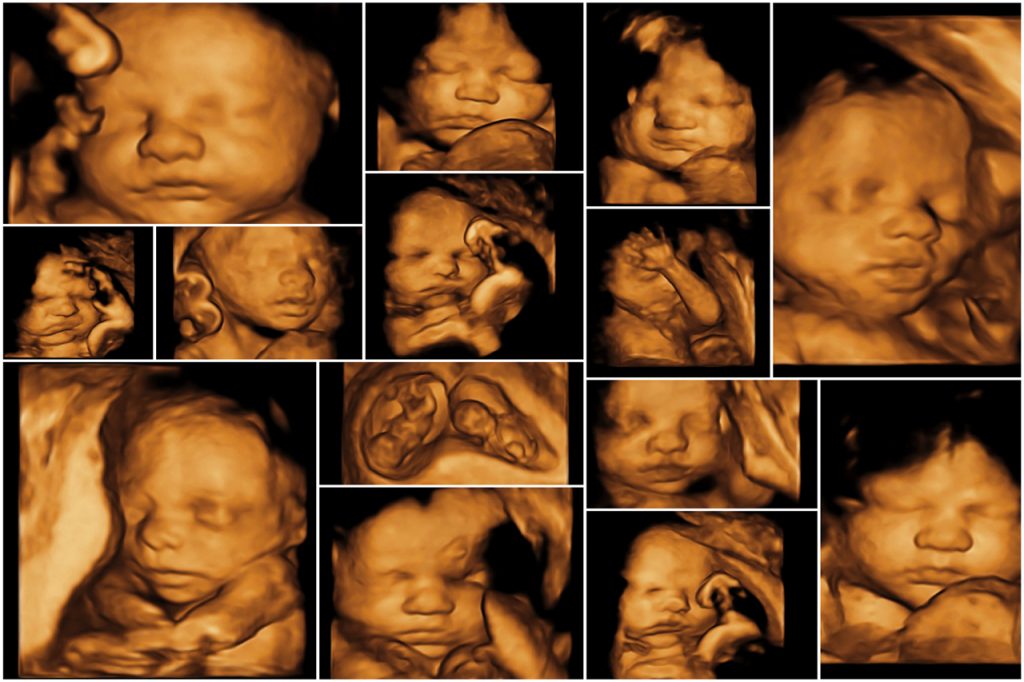

Los resultados de una ecografía se dividen en dos categorías, normales y anormales. Normales. El feto tiene el tamaño adecuado para su edad. La placenta es del tamaño esperado y no cubre el cuello uterino. Hay suficiente líquido amniótico en el útero. No se observan anomalías congénitas (de nacimiento).. En esta semana el feto ya ha alcanzado los 3-4 cm y su peso es de unos 5 gramos. Este rápido crecimiento fetal provoca la expansión del útero y hace que la mujer ya sienta su barriga más hinchada. Un gran cambio que sucede en la semana 10 es que el feto empieza a moverse: abre y cierra la boca, las manos y los pies.

Ecografia 4D Preguntas frecuentes Ecografia 4D y Medicina Fetal

Qué se evalúa en la ecografía del bebé de 3 meses Madres Hoy